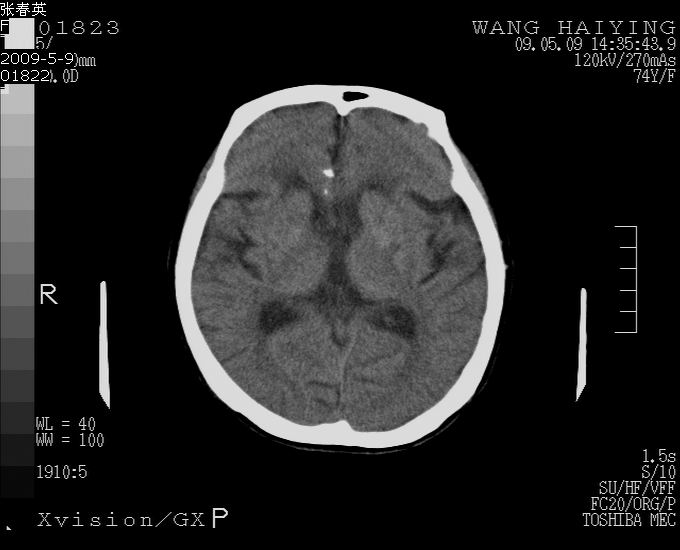

以下是引用bmw011在2009-5-9 18:25:00的发言:[br]脑内多发缺血、梗塞。

以下是引用余辉在2009-5-9 18:32:00的发言:[br]基底动脉稍扩张且右偏,其上方层面见高密度块影,考虑动脉瘤可能,建议增强,皮脑

以下是引用杀毒软件在2009-5-9 17:48:00的发言:[br]不排除动脉瘤可能,建议进一步检查。 [br]